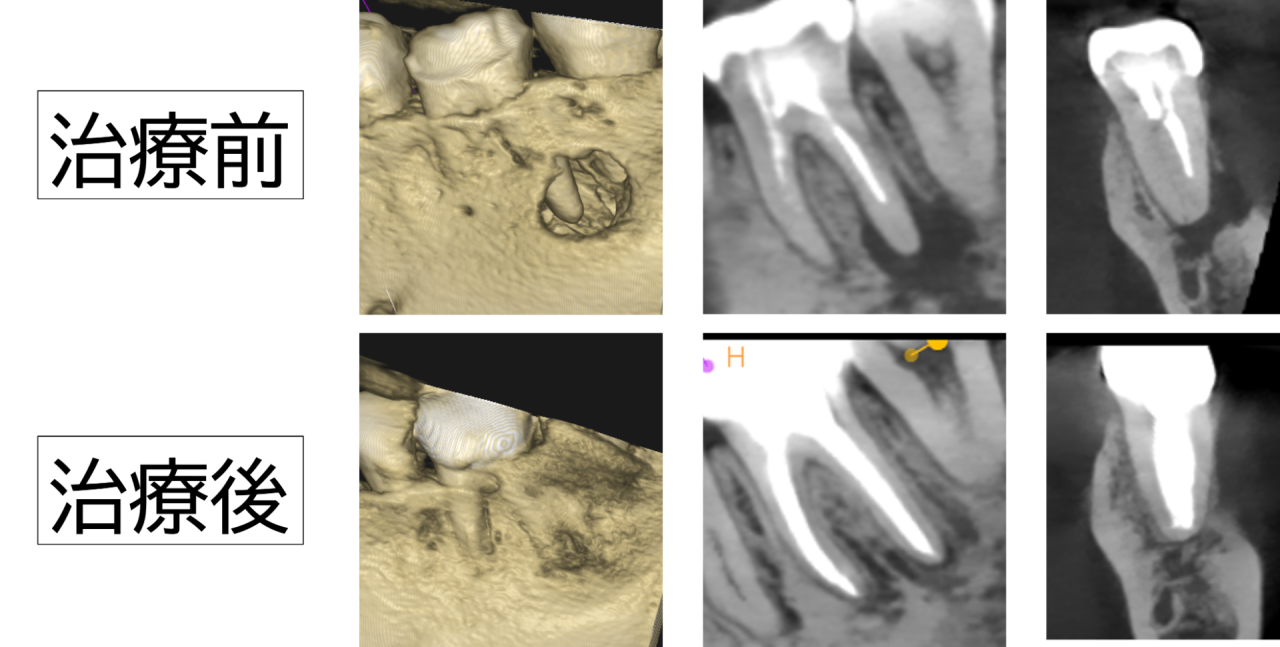

溶けた骨が再生した

治療から半年後のレントゲンでは、根の先の黒い影が縮小し、骨の回復・再生傾向が確認できました。自発痛や噛んだときの痛みは消失し、歯ぐきの腫れも落ち着いています。経過観察を続けながら、定期的なクリーニングと噛み合わせチェックを実施中です。